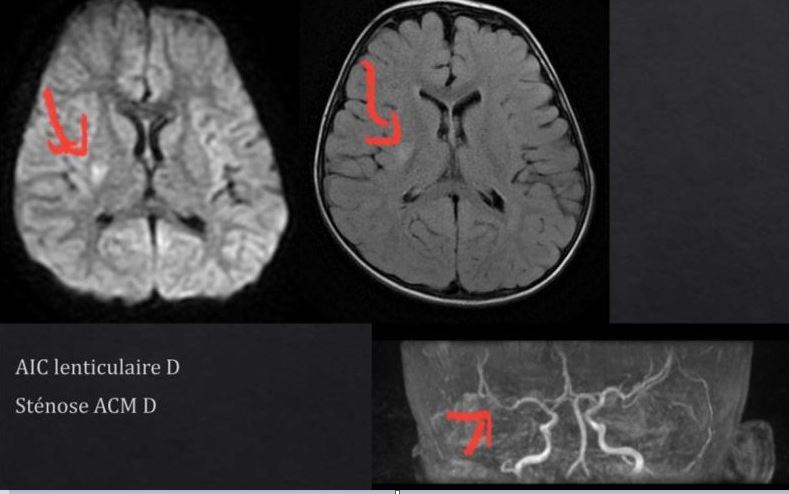

* IRM cérébrale : Détection d’un AVC ischémique profond droit

Dans le cas de Sarah, l’AVC a été attribué à une artériopathie (atteinte des artères secondaire à l’infection par la varicelle). L’artériopathie est la cause la plus fréquente d’infarctus cérébral de l’enfant.